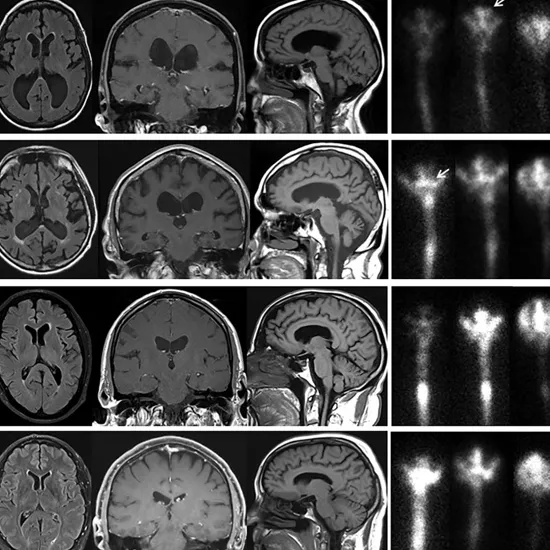

MRI Cisternography Head is a new kind of examining methodology to detect CSF Fistulae. These techniques prove more promising than CT Cisternography due to higher sensitivity.

MRI Cisternography Head is performed in one/ two sequences (Coronal and/or Sagittal) post-traditional MR Brain studies. Conventional MRI study includes fast spin-echo axial sequences. Complete scanning runs to 30- 60 minutes.